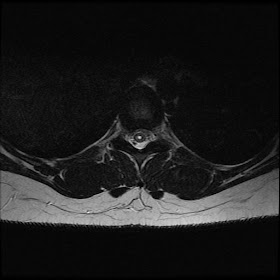

Syringohydromyelia